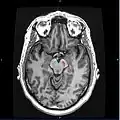

![]() Section through superior colliculus showing substantia nigra. | |

Horizontal MRI (T1 weighted) slice with highlighting indicating location of the substantia nigra.